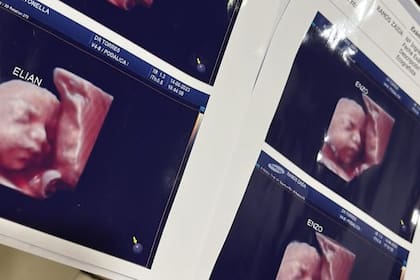

Denuncian que una clínica de Formosa usaba la misma ecografía para todas las embarazadas: “Nos estafó”

Cuando una joven embarazada subió a TikTok la ecografía del hijo que llevaba en su vientre no imaginó lo que se iba a generar. Inmediatamente, Antonella Roglan reconoció en esa imagen a quien creía que era su hijo. Ambas intentaron evitarlo, aunque después de un tiempo llegaron a una conclusión terrible. Al parecer, la clínica privada en la que se atendían, en Formosa, las había engañado: habría usado la misma ecografía con ellas y quizás con varias mujeres más.

Las fotos 5D de las imágenes se convirtieron para ellas en una pesadilla. No tienen dudas de que se trata de una “estafa”, según dio cuenta el sitio Noticias de Formosa. “Ya nos lo habían dicho, pero nos resistíamos a creer”, afirmó una de ellas. Hasta el momento, son cuatro las mujeres afectadas, según dijo Roglan en su cuenta de Twitter.

“Por ahora somos tres mamás a las que una clínica estafó con una foto de un bebé que no es el nuestro”, afirmó Roglan en su cuenta de Twitter. “Está de más decir que encima que cobran carísimo uno se va ilusionado por ver a su bebé y tener un lindo recuerdo. Estamos en busca de más mamás con el mismo bebé”, dijo.

Más tarde, la mujer comentó que habían descubierto que esa misma imagen se la habían dado a otra familia y le habían hecho creer que se trataba de una niña, según expresó. En los primeros casos, la imagen fue entregada a mamás que esperaban varones. Así, no tenían dudas de que habría varias personas afectadas.